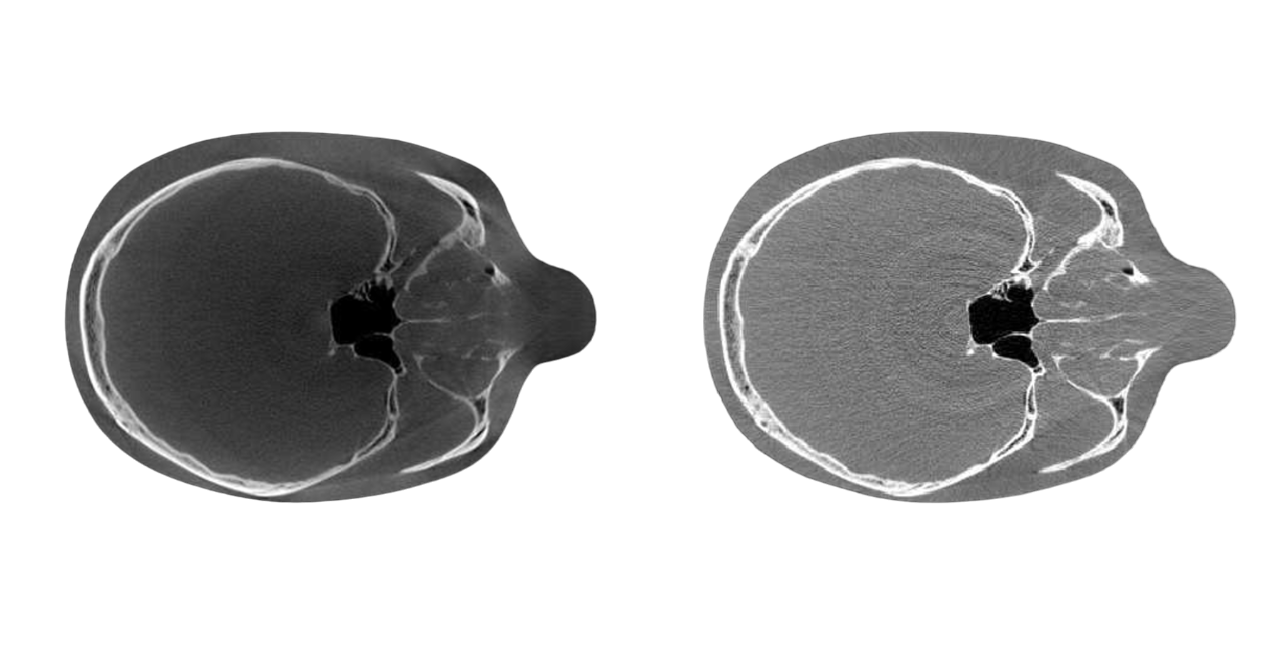

코스타의 xenoray cone beam CT는 2019년 4월 유럽 CE 인증 획득에 이어 2020년 9월 미국 FDA 승인을 받은 cone beam CT 중에서도 안정성과 정확성을 인증받은 탁월한 장비입니다.

3D cone beam CT의 장점

PAPAYA 3D CT, Panoramic이 결합된 통합 시스템으로 진료, 7.7초의 빠른 촬영속도로 피폭량 줄이면서 정확하고 세밀한 영상을 제공합니다.